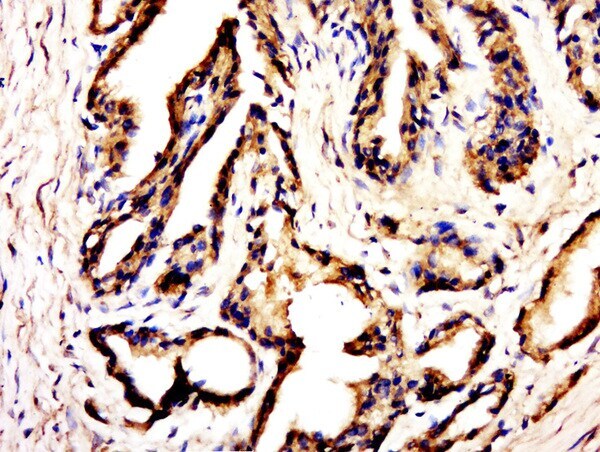

Supportive validation

- Submitted by

- Invitrogen Antibodies (provider)

- Main image

- Experimental details

- Paraformaldehyde-fixed, paraffin embedded rat kidney; Antigen retrieval by boiling in sodium citrate buffer (pH6.0) for 15min; Block endogenous peroxidase by 3% hydrogen peroxide for 20 minutes; Blocking buffer (normal goat serum) at 37°C for 30min; Antibody incubation with C20orf173 Polyclonal Antibody, Unconjugated (bs-15100R) at 1:500 overnight at 4°C, followed by a conjugated secondary for 20 minutes and DAB staining.